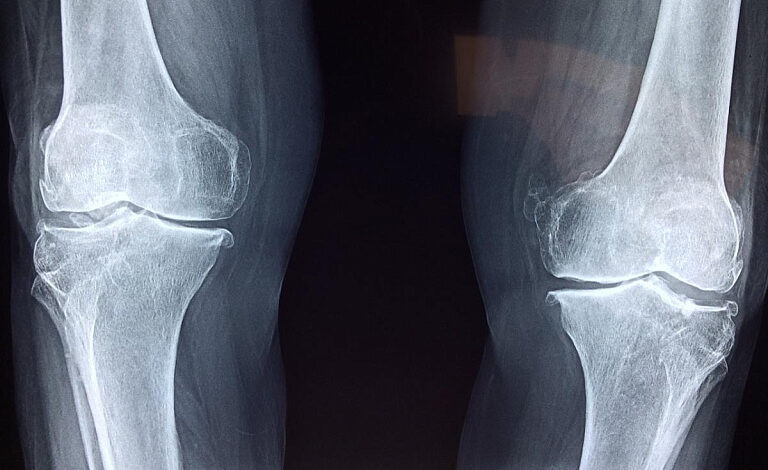

Он уточнил, что очередь по замене тазобедренного сустава составляет 11 779 человек, по коленным суставам – 14 058. Число необходимых замен тазобедренного сустава с 23 мая 2023 года сократилось на 17%, коленных – на 10% с той же даты.

Главный внештатный травматолог-ортопед Минздрава Михаил Герасименко тогда рассказал, что за 10 месяцев 2023 года в Беларуси проведено 7098 операций по замене тазобедренного сустава и 2216 – по замене коленного.

Но при этом, по данным на 1 ноября 2023 года, в листе ожидания на замену тазобедренного сустава находилось еще 11 485 человек. Сколько людей ждут эндопротезирования коленного сустава, специалист не уточнил.

Напомним, по данным на начало июня 2023 года, около 14 тыс. белорусов ожидали операции по замене тазобедренного сустава, еще 15 тыс. – коленного.